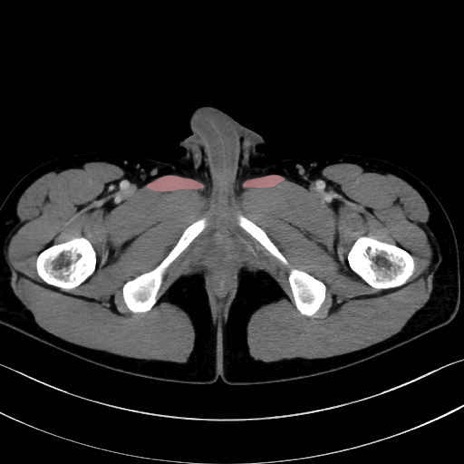

長内転筋(Adductor longus muscle)のCT画像の解剖

長内転筋 (Adductor longus)